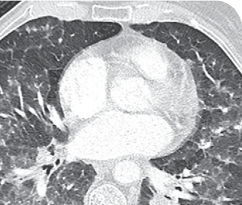

Response in primary and metastatic lesions1

Lung imaging of primary tumors.

SCAN 1: LUNG

SCAN 2: LUNG AND BONE

Images courtesy of Dr Maximilian Hochmair.